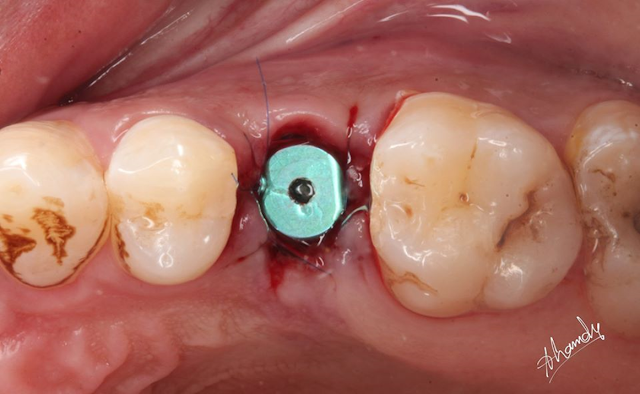

![]() |

| post extraction implant placement with healing abutment secured |